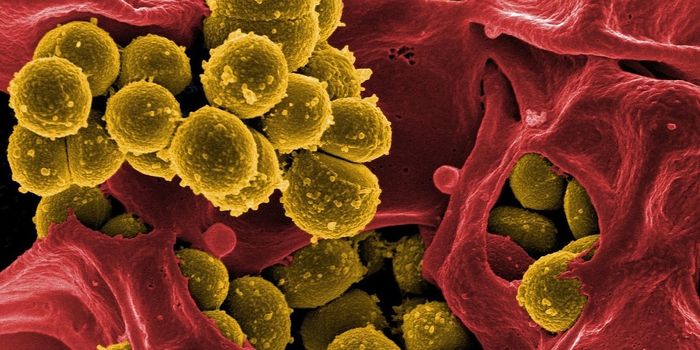

OCT 29, 2016Clinical & Molecular DXDespite frequent cleaning and sterilization, hospitals are notorious hotspots for germs and pathogens. And it’s no ...

SEP 20, 2023Clinical & Molecular DXHospitals are supposed to help sick people get healthy, but unfortunately, many hospitalized patients become sick with i ...

MAR 19, 2017MicrobiologyIt can be incredibly challenging to give a patient the proper treatment when they are infected by an antibiotic-resistan ...

OCT 18, 2019Health & MedicineMultidrug-resistant bacteria are frequently found in hospitals and long-term nursing facilities causing one of the large ...